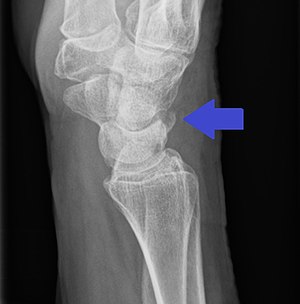

Triquetral avulsion fracture as seen on lateral X-ray of the wrist

It most commonly occurs as a result of a fall onto the hand or being pulled appart by an attached ligament.[3] Other causes may include a direct blow.[1] Diagnosis is generally based on wrist X-rays, though CT scaning can also be useful.[3] Types include dorsal cortical (most common), body, and palmer cortical.[4]